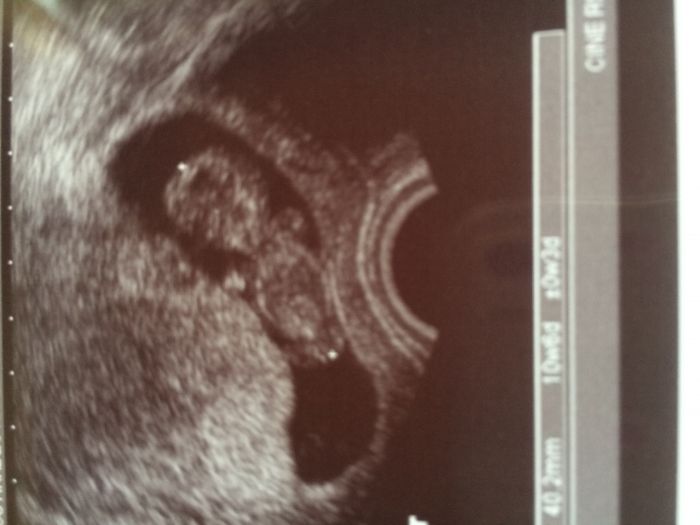

Holky, tak jen podávám info, dnes mám za sebou první část screeningu, brali mi krev a dělali kontrolní utz a za 14 dní jdu na velký utz a budeme mít rovnou výsledky. Náš prcek má už přes 4cm:-)

[1014521] super zprava. Krasny miminko

[1014524] Lentilko děkuji, je to krása:-)posunuli jsem se o 2 dny dopředu:-)...neboj, brzy se taky přidáš, třeba dřív než si myslíš:-)

Molupko krásné potvrzení